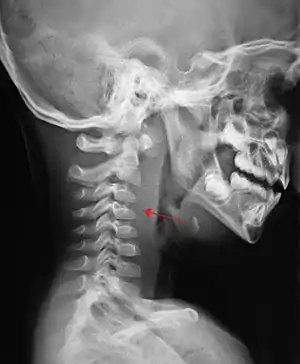

A computed tomography (CT) scan is the definitive diagnostic imaging test.[6]

Large retropharyngeal abscess as seen on CT